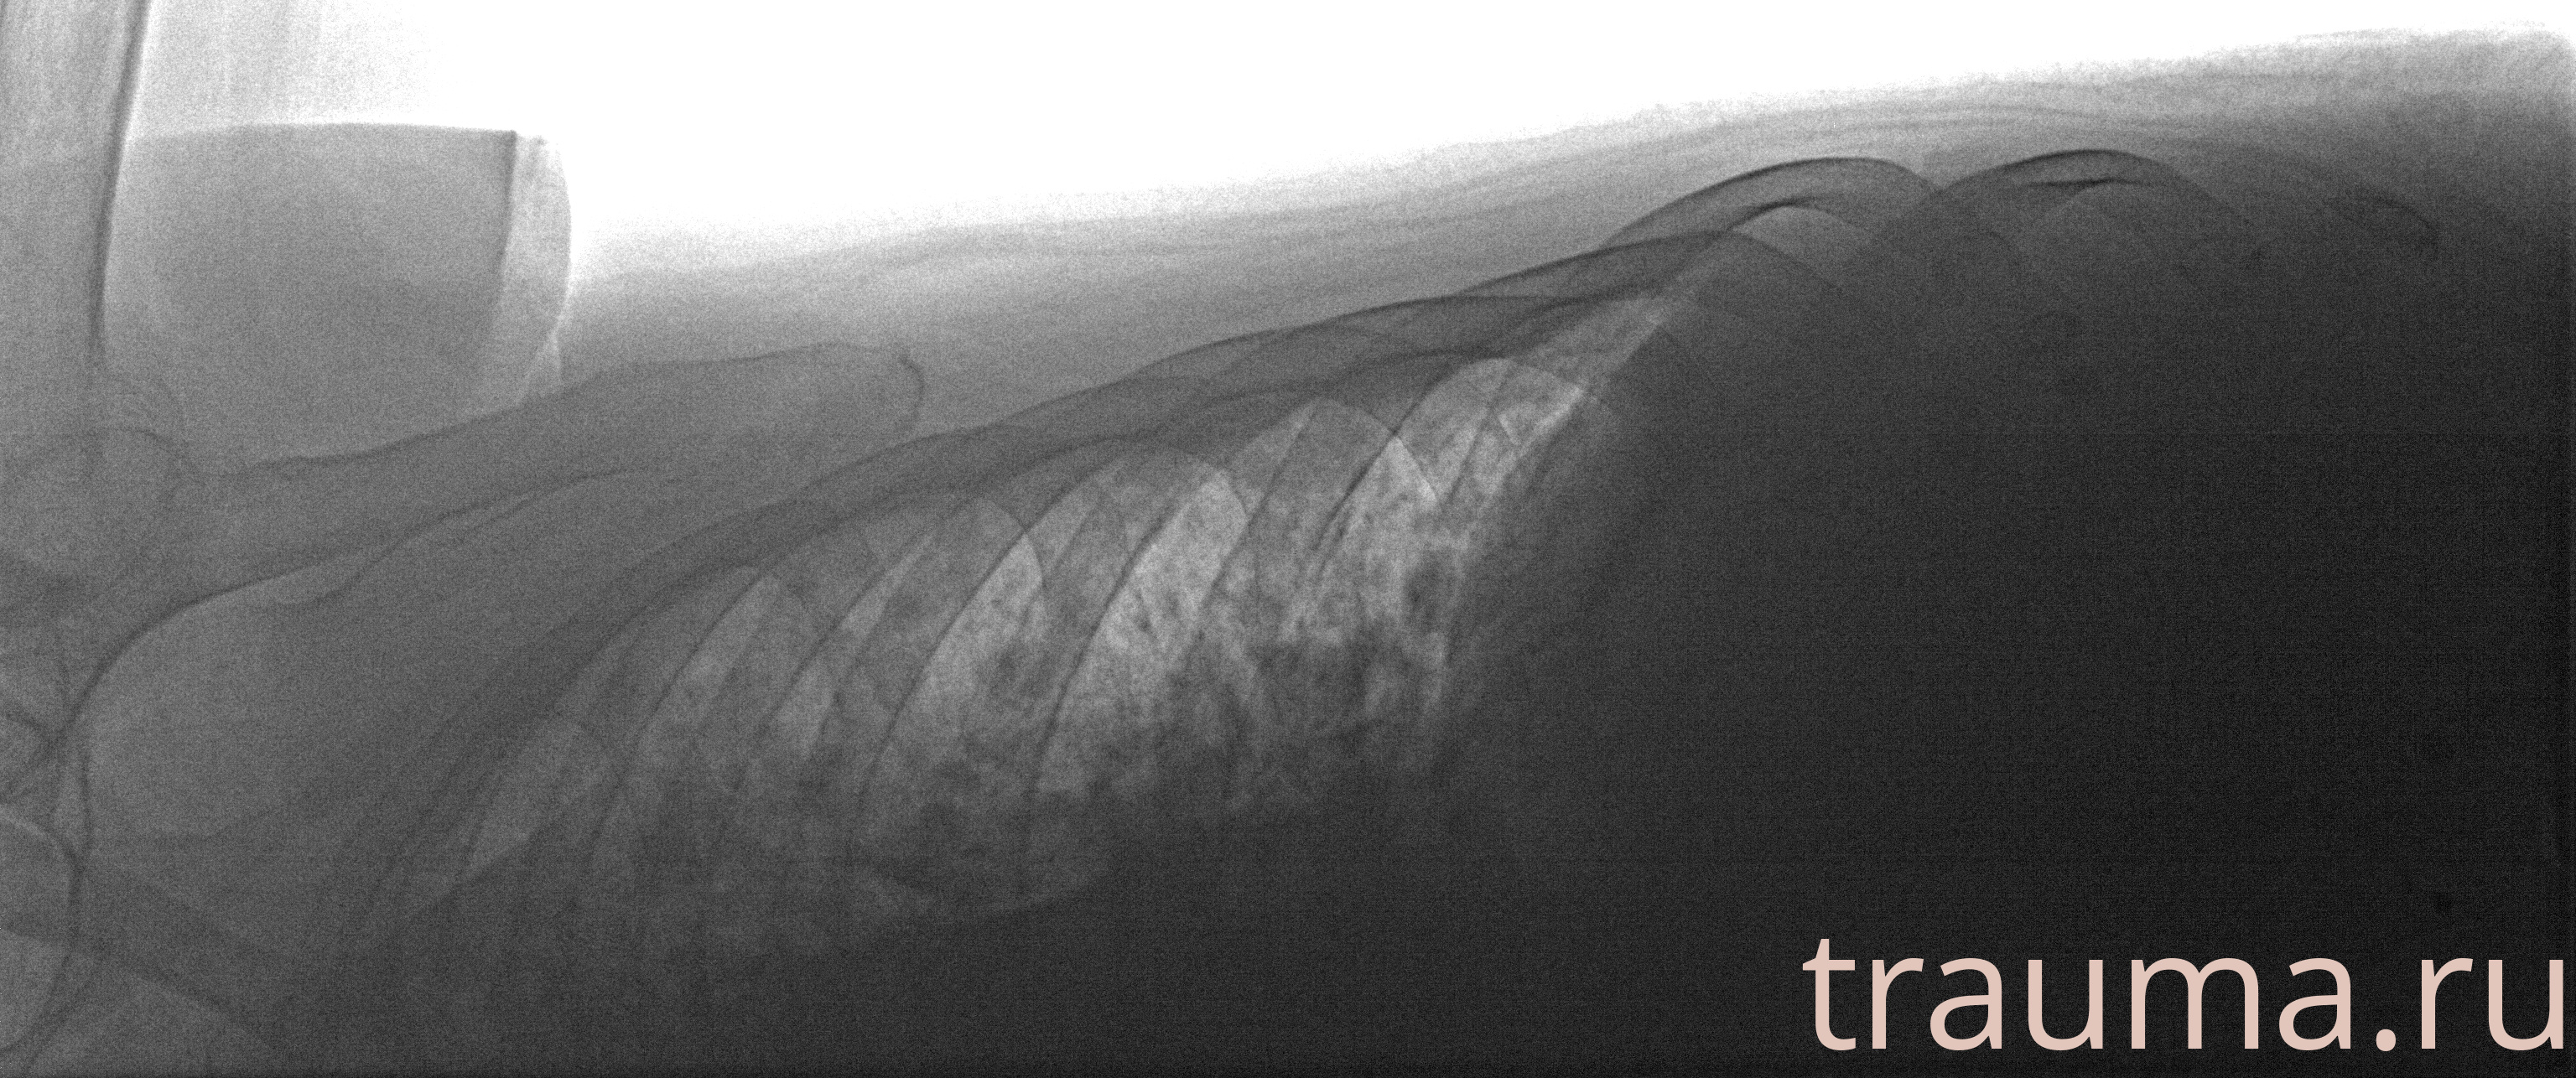

Рентген на дому: по вашему адресу приезжает врач-рентгенолог, травматолог-ортопед с мобильным рентгеновским аппаратом, проводит диагностику травмы или заболевания, делает необходимые рентгенограммы, дает рекомендации по дальнейшему лечению. Получить качественные снимки в домашних условиях возможно благодаря уникальной методике, разработанной МосРентген Центром для института  Склифосовского